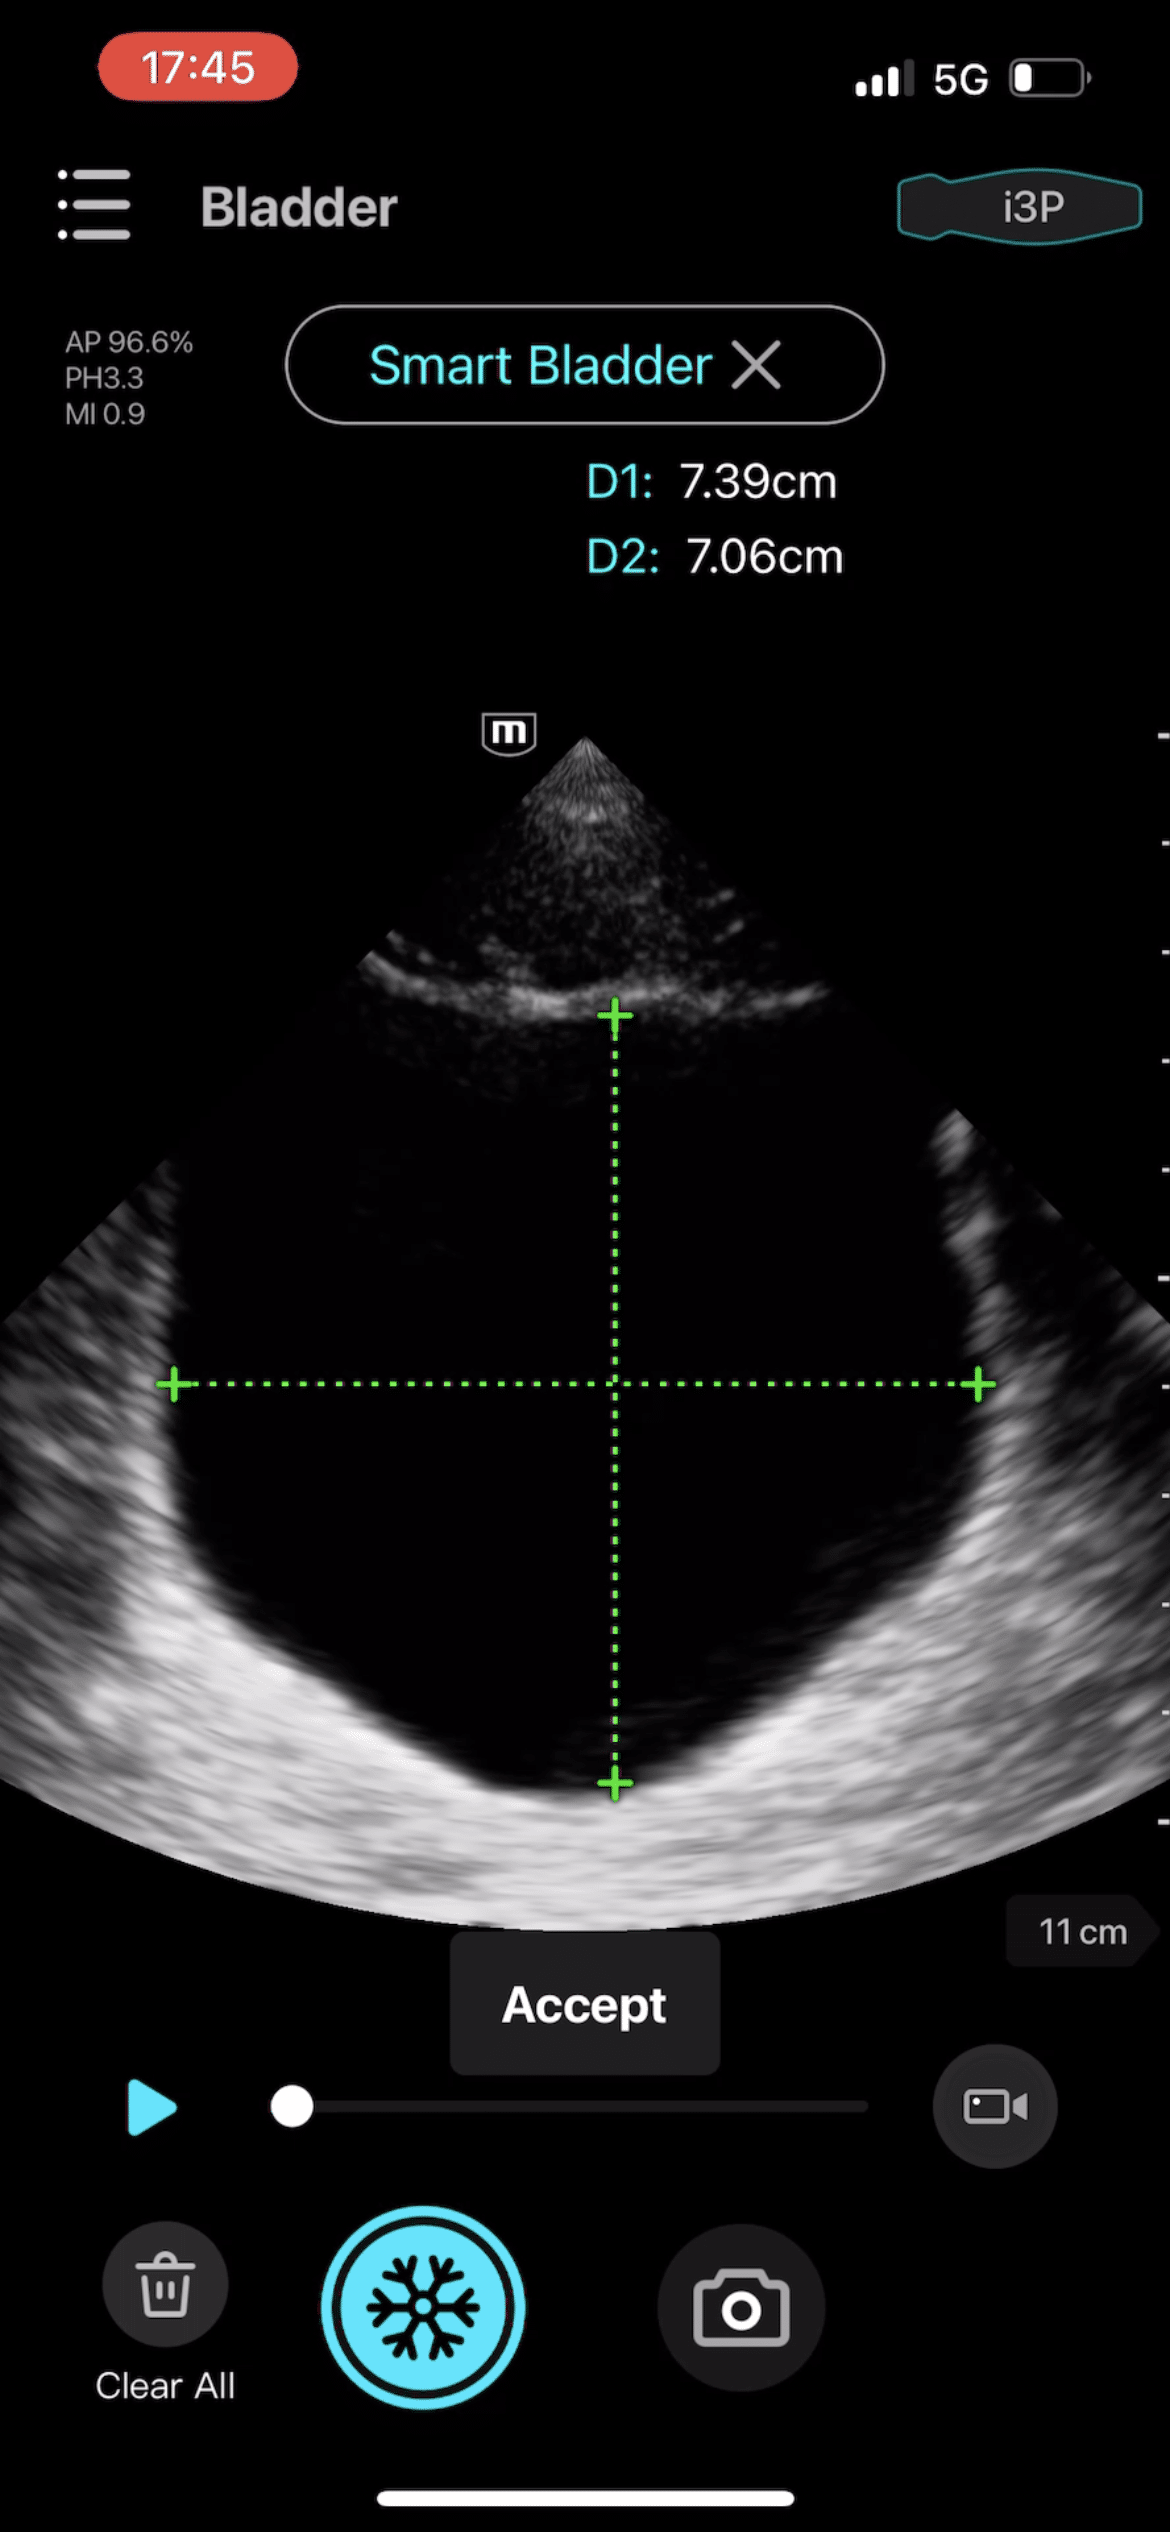

- Aortic Aneurysm (AAA), Bladder, OB/GYN, and Vascular

Clinical Images